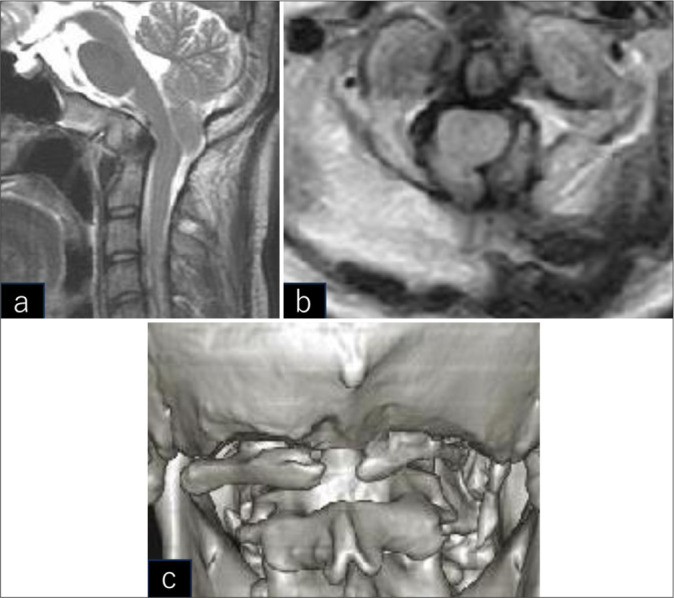

Case description: A 13-year-old child originally presented with headaches and CM1 and AA, for which he underwent a FMD without duraplasty. Seven years later, at the age of 20, he developed recurrent C1 stenosis attributed to dorsal bony proliferation of the lamina of the atlas. Following a secondary mini-open exoscopic decompression without duraplasty, he became asymptomatic.

Conclusion: For patients with CM1 without syringomyelia, recurrent stenosis may be successfully managed with repeated mini-open exoscopic bony decompression.